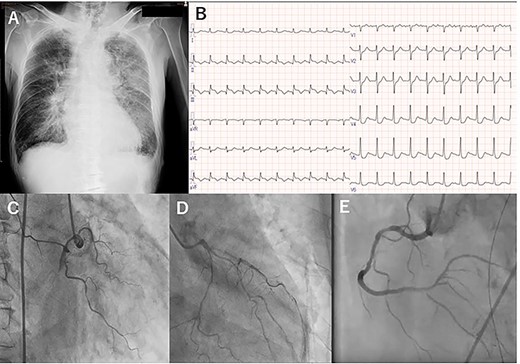

A 76-year-old man presenting with acute onset dyspnea, chest pain and loss of consciousness was referred to our institution. He was a current smoker and had hypertension treated with several antihypertensive agents. His vital signs on admission were blood pressure 117/58 mmHg with support of 7γ of dopamine, heart rate 121 beats/min and SpO2 94% with oxygen at 6 L. Cardiac and pulmonary auscultation were unremarkable on admission. Congestive heart failure (CHF) was found on the initial chest X-ray (Fig. 1A). Troponin T was elevated (4.2 ng/mL), as were CK (722 U/L) and CK-MB (86.4 U/L). The electrocardiogram showed ST elevations in leads II, III and aVF, consistent with acute inferior MI (Fig. 1B). Due to on-going cardiogenic shock, he was treated with an intra-aortic balloon pump (IABP) and mechanical ventilation. Emergent coronary artery angiography showed a completely occluded right coronary artery (RCA), 75% stenosis in the proximal-to-mid portion of the LAD and 90% stenosis in the proximal portion of the left circumflex artery (Fig. 1C and D). The occluded lesion of the RCA was treated with drug-eluting stents (Fig. 1E), and he was transferred to the intensive care unit (ICU).

Preoperative chest X-ray (A), electrocardiogram (B) and coronary angiography: right coronary (C), and left anterior descending and left circumflex (D), and right coronary artery (E).